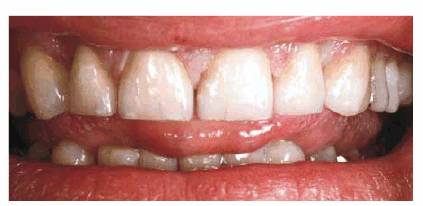

SHAPING FOUR CROWNS TO CLOSE A DIASTEMA

PROBLEM: A 20-year-old female presented with diastemas between her

maxillary lateral and central incisors (Figure 23-16A). She had a poorly fitting crown on the

Figure 23-16A and B: This 20-year-old student was unhappy with the appearance of her smile. In addition to the multiple spaces, there was a labial flare to the teeth that made them look shorter than they actually were.

TREATMENT: In cases where diastemas are evenly distributed between the

central and lateral incisors (Figure 23-16B), the best solution is laminating or crowning

appearance of the centrals. Proportionally contoured and shaped crowns were

constructed for the incisors and seated in place (Figures 23-16C, and 23-16D).

RESULT: As previously stated, orthodontics is the preferred treatment of

choice in closing diastemas involving normal-sized teeth. However, when

correction by restoration is chosen, it is best to use an even number of teeth

to close diastemas. Although the above case was successfully treated with four

porcelain-fused-to-metal crowns, porcelain laminate veneering would probably be

the treatment of choice today.